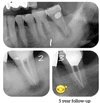

Implant tedavisi